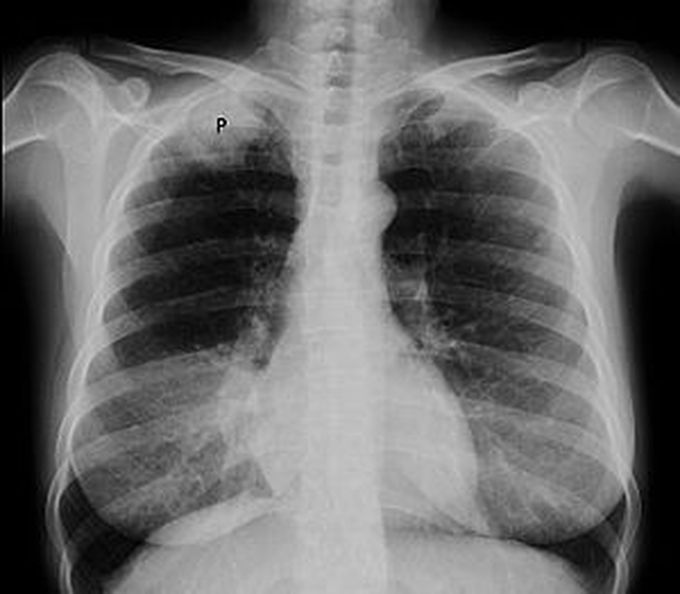

Superior sulcus tumors give rise to ipsilateral shoulder pain, pain in ipsilateral arm, paresis, paresthesia, and atrophic thenar muscle. This constellation of signs and symptoms attributed to superior sulcus lung tumors is called Horner’s syndrome. Non-small cell lung carcinoma is most commonly associated with Pancoast syndrome. The condition is treated with chemotherapy and radiotherapy. This regime is followed by surgical resection. Reference: https://www.ncbi.nlm.nih.gov/books/NBK482155/ Image via: https://en.wikipedia.org/wiki/Pancoast_tumor